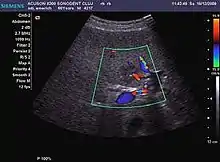

Peripheral vascular pattern of the lesion is observed in colon cancer metastasis (CEUS).

Lesion hyperenhancement in ovarian cancer liver metastasis is seen during the arterial phase.

US examination is required to detect liver metastases in patients with oncologic history. In addition, the method can incidentally detect metastases in asymptomatic patients. Early identification (small sizes, small number) is important to establish an optimal course of treatment which can be complex (chemotherapy, radiofrequency ablation, surgical resection) but welcomed. In addition, discrimination of synchronous lesions that have a different nature is also important knowing that up to 25–50% of liver lesions less than 2 cm detected in cancer patients may be benign . US sensitivity for metastases detection varies depending on the examiner's experience and the equipment used and ranges between 40 and 80% . Sensitivity is conditioned by the size and acoustic impedance of the nodules. For a lesion diameter below 10 mm US accuracy is greatly reduced, reaching approx. 20%. Other elements contributing to lower US performance are: excessive obesity, fatty liver disease, hypomobility of the diaphragm, and certain patterns of hyperechoic or isoechoic metastases that can be overlooked or can mimic benign conditions. Conventional US appearance of metastases is uncharacteristic, consisting of circumscribed lesions, with clear, imprecise or "halo" delineation, with homogeneous or heterogeneous echo pattern. They can be single (often liver metastases from colonic neoplasm) or multiple. Echogenity is variable. When increased, they can compress the bile ducts (which may be dilated) and the liver vessels. Liver involvement can be segmental, lobar or generalized. In this situation a pronounced hepatomegaly occurs. Generally, metastases have non-characteristic Doppler vascular pattern, with few exceptions (carcinoid metastases). Cyst-adenocarcinoma metastases due to semifluid content may have a transonic appearance. When increasing, they can result in central necrosis. CEUS examination is a real breakthrough for detection and characterization of liver metastases.

Increased performance is based on identifying specific vascular patterns during the arterial phase and seeing metastases in contrast to normal liver parenchyma during the sinusoidal phase. CEUS increased accuracy is due to the different behavior of normal liver parenchyma (captures CA in Kuppfer cells) against tumor parenchyma (does not contain Kuppfer cells, therefore CEUS appearance is hypoechoic). To this adds the particularities of intratumoral circulation represented by a reduced arterial bed compared to that of the surrounding normal liver and the absence of the portal vessels . In terms of vascularity, metastases can be hypovascular (in gastric, colonic, pancreatic or ovarian adenocarcinomas) with hypoechoic pattern during arterial phase, and similar during portal venous and late phases, respectively hypervascular (neuroendocrine tumors, malignant melanoma, sarcomas, renal, breast or thyroid tumors) with hyperechoic appearance during arterial phase, with washout during the portal venous phase and hypoechoic pattern 30 seconds after injection.